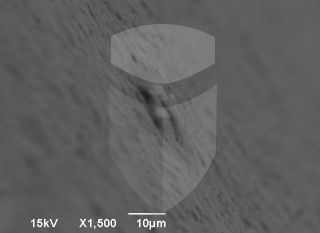

Implante 5 estrelas. Boa usinagem, algumas poucas rebarbas e ótima limpeza.

Topografia/rugosidade:

Marca e tipo de microscópio:

Jeol JSM 6390 Lv